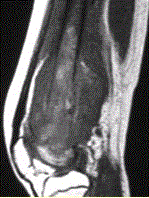

问题 患者男,16岁,左大腿下部疼痛伴肿胀2个月,逐渐加重。自感左膝上方胀痛,尤以夜间为著,伴行走困难。既往史及家族史无特殊。查体:左大腿下部明显肿胀,皮温较对侧升高。碱性磷酸酶明显增高。股骨平片及MRI见下图。 你认为对定性诊断有价值的征象是

选项 A.病变边缘模糊,内部信号不均 B.病变边缘骨皮质完整 C.病变周围可见软组织肿块 D.病变边缘可见骨膜反应,Codman三角形成 E.MR示病变周围骨髓明显水肿 F.病变内未见钙化影

答案 ACDEF